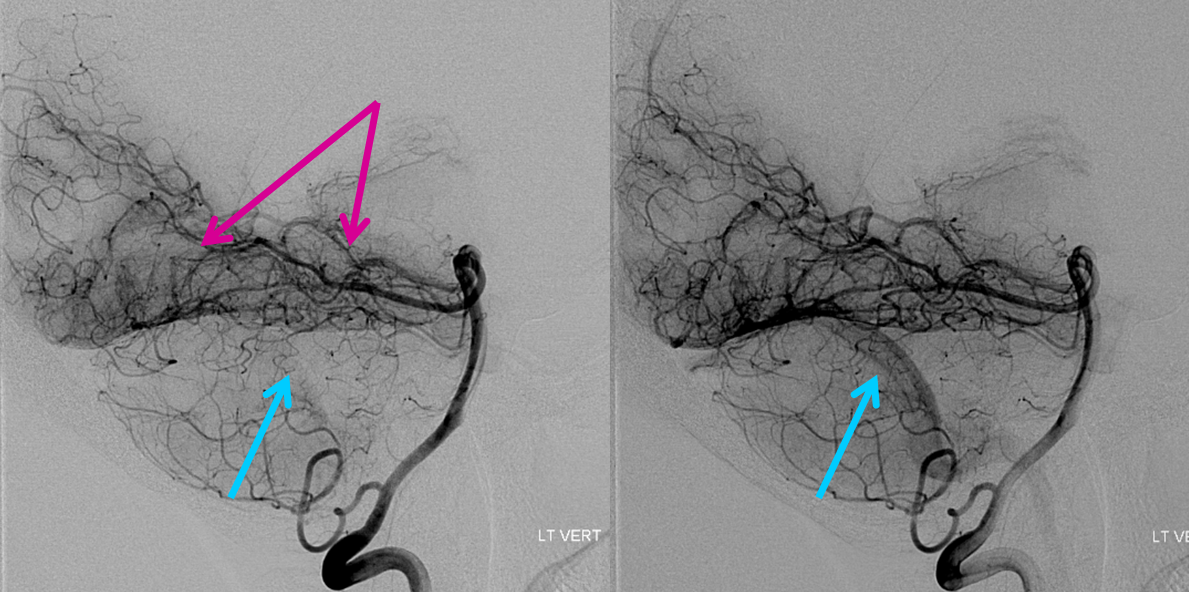

An angio was ordered. Below are sequential DSA images of the left vertebral artery injection. Look at the tremendous hyperemia in the left mesial temporo-occipital area (pink arrows), with physiologic shunting as evidenced by premature appearance of the transverse sinus (blue arrows). This is essentially the picture of parenchymal inflammation — just like any other part of the body, where inflammation makes tissues hot and hypervascular, so it is here. Of course, the differential is any kind of inflammatory/infectious process; in this clinical context, we went with encephalitis.